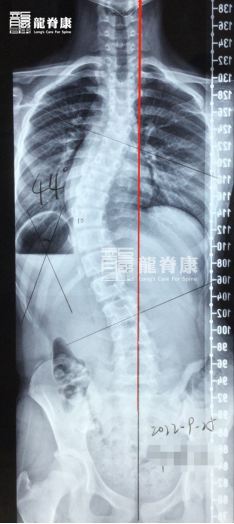

近年来,多地学校已开展脊柱侧弯筛查,不少孩子被查出“姿态不良”“脊柱侧弯”等问题。但很多家长却误以为:“只是坐姿不好,戴个背背佳就能解决”,或是“长大自然就好了”。殊不知,这种忽视正在让黄金治疗期悄悄溜走!

要知道,脊柱侧弯在青春期发育高峰恶化速度最快。此时骨骼快速生长,侧弯角度每半年可能增加5°-10°,一旦错过干预时机,最终可能不得不面对手术风险。